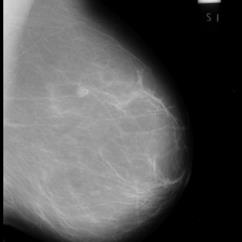

Recent advances in general medical AI have made significant strides, but existing models often lack the reasoning capabilities needed for complex medical decision-making. This paper presents GMAI-VL-R1, a multimodal medical reasoning model enhanced by reinforcement learning (RL) to improve its reasoning abilities. Through iterative training, GMAI-VL-R1 optimizes decision-making, significantly boosting diagnostic accuracy and clinical support. We also develop a reasoning data synthesis method, generating step-by-step reasoning data via rejection sampling, which further enhances the model's generalization. Experimental results show that after RL training, GMAI-VL-R1 excels in tasks such as medical image diagnosis and visual question answering. While the model demonstrates basic memorization with supervised fine-tuning, RL is crucial for true generalization. Our work establishes new evaluation benchmarks and paves the way for future advancements in medical reasoning models. Code, data, and model will be released at \href{https://github.com/uni-medical/GMAI-VL-R1}{this link}.